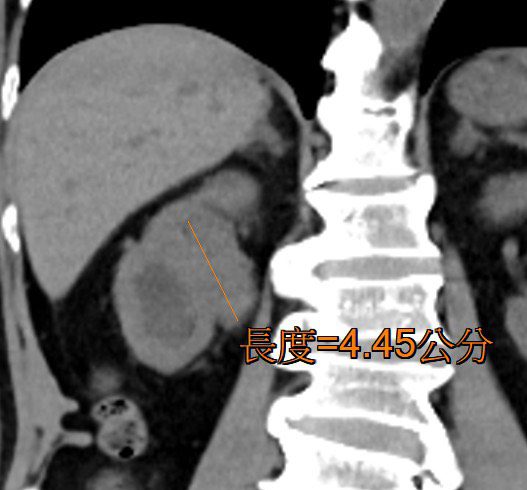

收治病患的高醫岡山醫院泌尿科主治醫師陳怡璇表示,抽血發現李先生血色素低至3.1 g/dL(正常值約為12-16 g/dL),幾近重度貧血,經電腦斷層掃描檢查發現,其右側腎臟至輸尿管內,有一顆近5公分的大型腫瘤持續出血,診斷為泌尿上皮癌。所幸經緊急手術切除腎臟及輸尿管,術後恢復良好,血色素也逐步回升至正常,持續於門診追蹤。